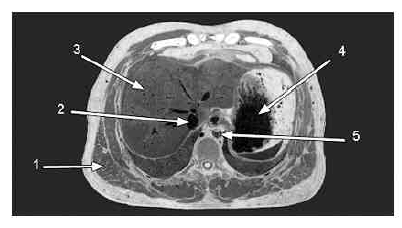

A figura acima mostra a fotografia de um corte anatômico realizado em cadáver. Considerando os dados mostrados na figura, julgue os itens a seguir.

A seta 5 indica a aorta descendente.

A seta 4 indica a cavidade interna de um órgão.

Provas

A seta 3 indica um órgão capaz de realizar trocas gasosas.

A seta 2 indica a traquéia.